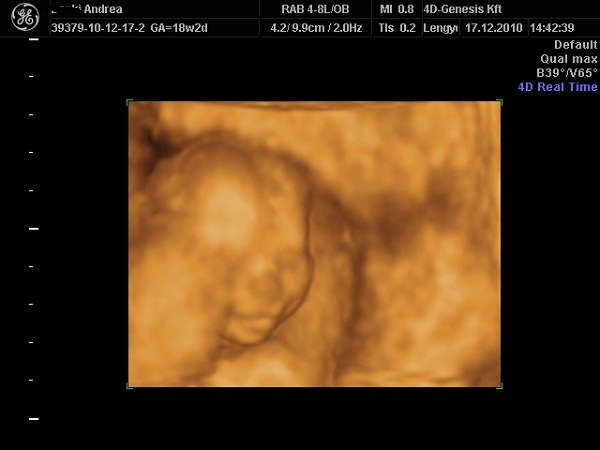

Pocaklakóm

Pocaklakóm